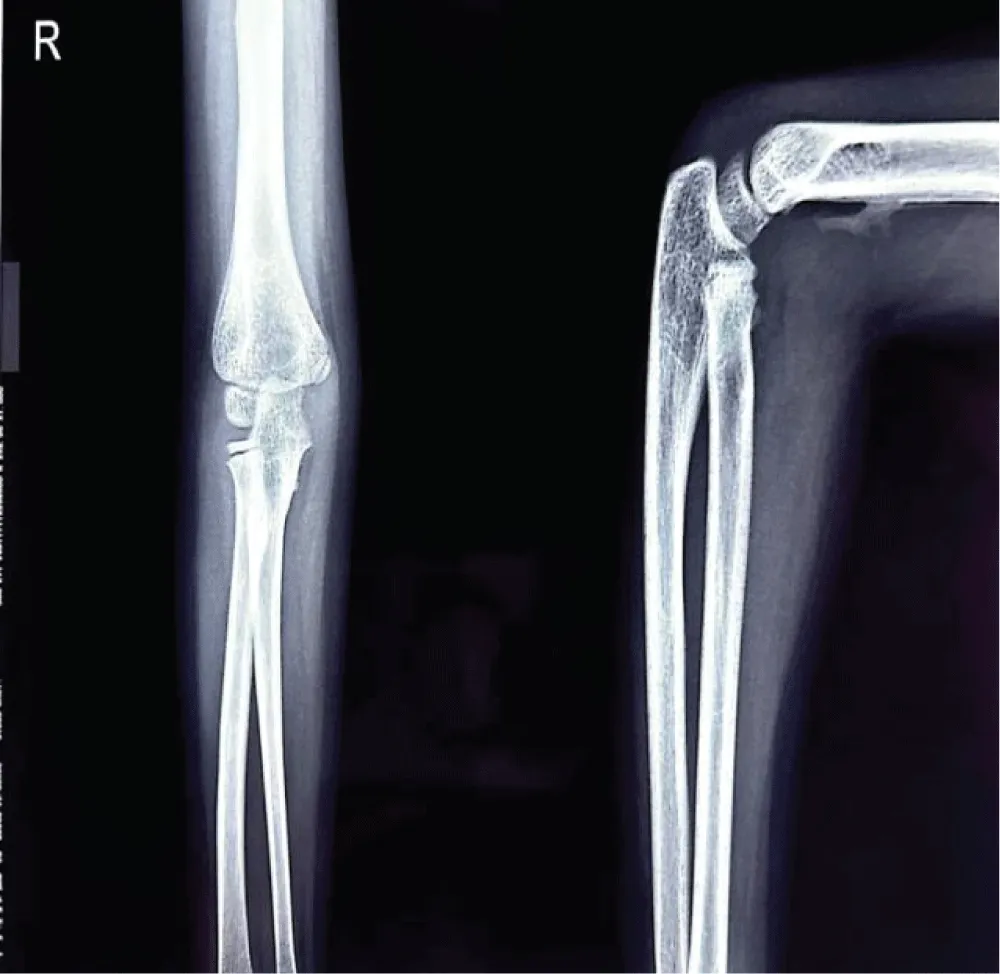

Radiograph of the elbow joint revealed a well-defined calcified mass parallel to the humerus, with a convex shape extending along the supracondylar region with the classical features of heterotopic ossification. The patient guardians declined further advanced imaging studies, including MRI, citing personal reasons. Consequently, the diagnosis of Myositis Ossificans Traumatica was made based exclusively on radiographic findings.

Radiological imaging showed residual heterotopic ossification along the humerus, indicating incomplete resolution. Multiple radiographs of the right upper limb-including the arm, forearm, and elbow joint were taken during outpatient visits at the patient’s convenience and were compared over time to monitor progress (figure 7,8). A well-visualized radiograph obtained 10 months after the initial injury showed near-complete resolution of the heterotopic ossification (Figure 9).